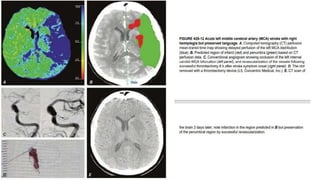

• Endovascular therapy with mechanical thrombectomy :

• for patients in whom fibrinolysis is ineffective or contraindicated.

Within 6-16hrs post event

• 4 devices have been approved :

1. Merci retriever

2. Penumbra system

3. Solitaire FR Revascularization Device

4. Trevo